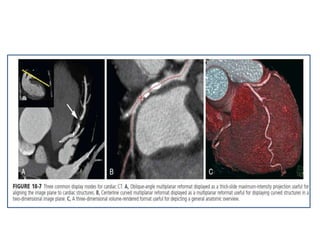

Cardiac CT provides high accuracy for evaluation of coronary bypass

grafts owing to their large size, often limited extent of calcified

atherosclerosis, and limited mobility, as shown in the oblique multiplanar

reformat (A) and three-dimensional volume-rendered reformat (B).

Cardiac CT provideshigh accuracy for evaluation of coronary bypass grafts owing to their large size, often limited extent of calcified atherosclerosis, and limited mobility, as shown in the oblique multiplanar reformat (A) and three-dimensional volume-rendered reformat (B).